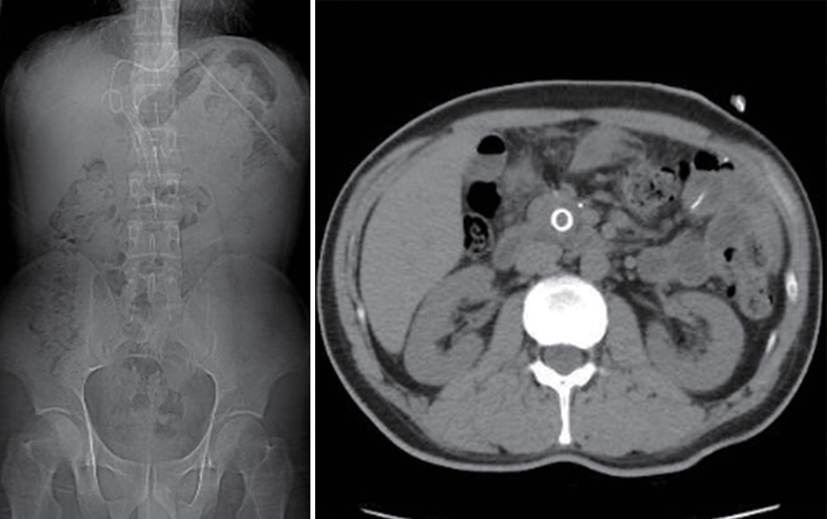

Value of internal stratification analysis of abdominal wall muscles in predicting complications after orthotopic liver transplantation

Xin SHI, Chongxiao LIANG, Bei ZHANG, Jiping WANG

2025, 41(2): 314-321. DOI: 10.12449/JCH250218

Abstract(741) HTML (353) PDF (3265KB)(54)

Abstract:

Objective  To divide the muscle into different subzones according to different density ranges using the stratified analysis on the basis of myosteatosis, and to investigate the effect of muscle density changes on complications (Clavien-Dindo grade ≥Ⅲ) after orthotopic liver transplantation (OLT).  Methods  A retrospective analysis was performed for the medical records of 145 patients who underwent OLT in The First Hospital of Jilin University from May 2013 to September 2020, and with the plain CT scan images of the largest level of lumbar 3 vertebrae of each patient as the original data, Neusoft Fatanalysis software was used to measure related muscle parameters. The independent-samples t test was used for comparison of normally distributed continuous data between two groups, and the Mann-Whitney U test was used for comparison of non-normally distributed continuous data between two groups. The chi-square test or Fisher test was for comparison of categorical data between two groups. RIAS software was used to extract clinical features and perform analysis and modeling, and three machine learning models of logistic regression (LR), support vector machine (SVM), and random forest (RFC) were constructed. The receiver operating characteristic (ROC) curve, the calibration curve, and the decision curve were plotted for each model to calculate the area under the ROC curve (AUC), sensitivity, specificity, precision, F1 score, and accuracy.  Results  The three machine learning models of LR-C, SVM-C, and RFC-C were established based on the 7 clinical features before muscle stratification analysis, among which the RFC-C model had an AUC of 0.803, a sensitivity of 0.588, and a specificity of 0.778 in the test set. Among the models of LR-CS, SVM-CS, and RFC-CS established based on the 16 clinical features after muscle stratification analysis, the LR-CS and SVM-CS models had an AUC of 0.852 in the test set, with a sensitivity of 0.765 and 0.706, respectively, and a specificity of 0.889 and 0.926, respectively. Comparison of the AUC, sensitivity, specificity, precision, F1 score, and accuracy of each model in the test set before and after muscle stratification analysis showed that there were improvements in the parameters of the predictive model after muscle stratification analysis. Comparison of the decision curves and calibration curves of each predictive model showed that the LR-CS and SVM-CS models had good efficacy in predicting postoperative complications (Clavien-Dindo grade≥Ⅲ) in OLT patients.  Conclusion  On the basis of myosteatosis, the division of the muscle into different subzones according to different densities using the stratified analysis has a certain value in predicting postoperative complications in patients with OLT.